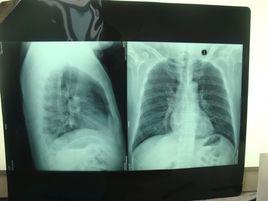

2.1 胸片的特點 : COP最常見的影像學表現是雙側或單側的實變影。通常呈斑片狀分布,少數病例可能限定於胸膜下區。10%~50%的病例可見小結節影。少數患者表現為網結影。大約15%的病例影像學表現為大結節影(>1 cm)。將近75%的病例肺容積正常,其餘患者的肺容積縮小。

隱源性機化性肺炎2.2 CT的特點 :90%的COP患者CT表現為氣腔實變。將近50%的病例CT顯示病變沿胸膜下或支氣管周圍分布,以下肺區更明顯。當出現實變就能見到支氣管氣像。實變區常見輕度柱狀支氣管擴張。將近50%的病例常出現沿支氣管血管分布的小結節影。大約60%的病例出現磨玻璃影,通常與肺實質相伴隨。胸腔積液罕見,大多數COP患者經治療後影像學改善。然而未經治療時,一個部位的肺實質異常可能消散或擴大,甚至出現在新的部位。